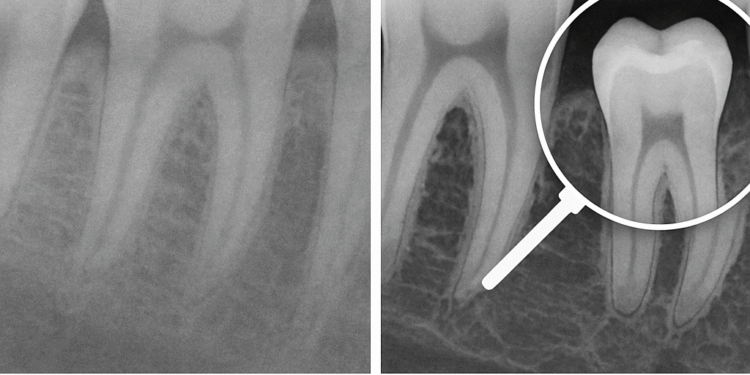

Uno de los pilares de este enfoque es el diagnóstico por imagen. La radiografía panorámica digital, por ejemplo, sigue siendo una herramienta muy utilizada para la primera valoración porque permite observar de manera global dientes, hueso y estructuras relevantes. En su versión digital, facilita la visualización, el almacenamiento y la comunicación clínica. Para pacientes que quieren informarse antes de su cita, La Clínica Dental publicó una guía práctica sobre el tema: https://laclinicadental.org/rayos-x-panoramicos-digitales-vs-convencionales-beneficios-y-como-funcionan/.